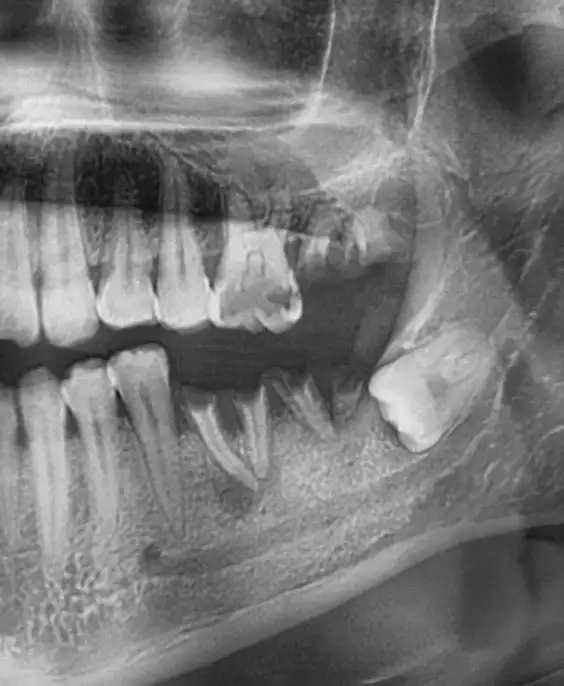

Детальний Огляд: Панорамний знімок зубів у Броварах

Болить зуб мудрості при натисканні